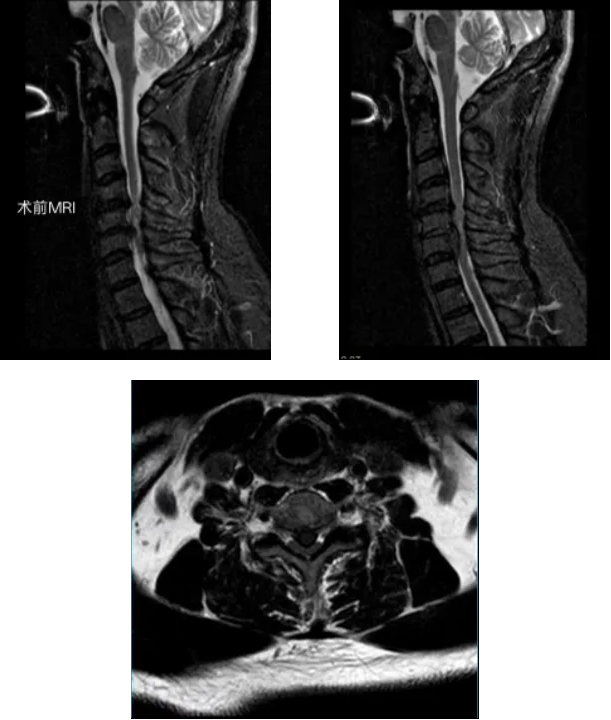

经详细问诊与影像检查,李永革主任很快锁定了“元凶”:颈椎MRI显示,徐先生的颈4/5、颈5/6、颈6/7椎间盘突出,其中颈5椎间盘已脱出,严重压迫脊髓,确诊为脊髓型颈椎病。